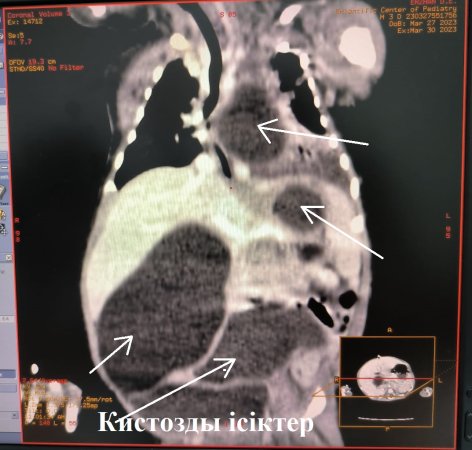

A huge cyst occupied the entire left chest, with compression of the left lung, the child had symptoms of respiratory failure from birth. Also, there were cystic formations in the abdominal cavity, as a result, the stomach was enlarged in volume, creating increased pressure in the abdominal cavity, with impaired stool discharge.

On the basis of computed tomography, a preliminary diagnosis was made: multiple doubling of the digestive system, thoracoabdominal form. Doubling of the esophagus, doubling of the intestines. Within five days, the condition was corrected. Surgical treatment was performed urgently, thoracotomy on the left, excision of the doubled part of the esophagus, laparotomy by excision of the duodenum duplication and resection of the tubularly doubled portion of the small intestine with anastomosis were performed at the same time.